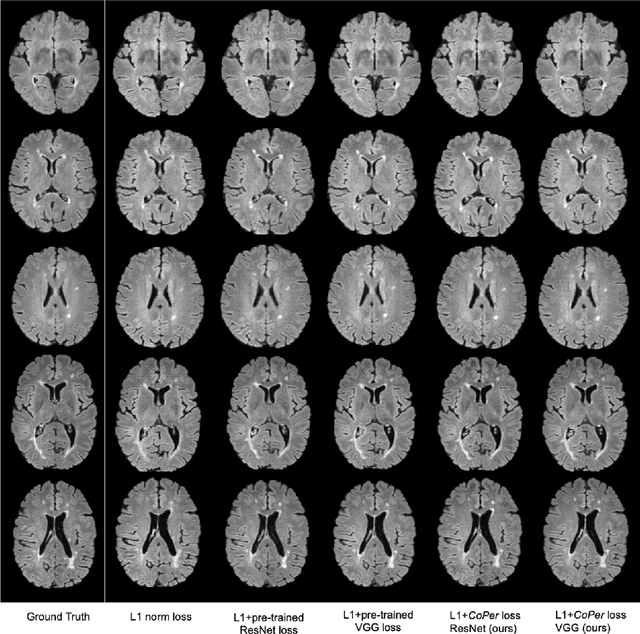

Abstract:Quantifying the perceptual similarity of two images is a long-standing problem in low-level computer vision. The natural image domain commonly relies on supervised learning, e.g., a pre-trained VGG, to obtain a latent representation. However, due to domain shift, pre-trained models from the natural image domain might not apply to other image domains, such as medical imaging. Notably, in medical imaging, evaluating the perceptual similarity is exclusively performed by specialists trained extensively in diverse medical fields. Thus, medical imaging remains devoid of task-specific, objective perceptual measures. This work answers the question: Is it necessary to rely on supervised learning to obtain an effective representation that could measure perceptual similarity, or is self-supervision sufficient? To understand whether recent contrastive self-supervised representation (CSR) may come to the rescue, we start with natural images and systematically evaluate CSR as a metric across numerous contemporary architectures and tasks and compare them with existing methods. We find that in the natural image domain, CSR behaves on par with the supervised one on several perceptual tests as a metric, and in the medical domain, CSR better quantifies perceptual similarity concerning the experts' ratings. We also demonstrate that CSR can significantly improve image quality in two image synthesis tasks. Finally, our extensive results suggest that perceptuality is an emergent property of CSR, which can be adapted to many image domains without requiring annotations.